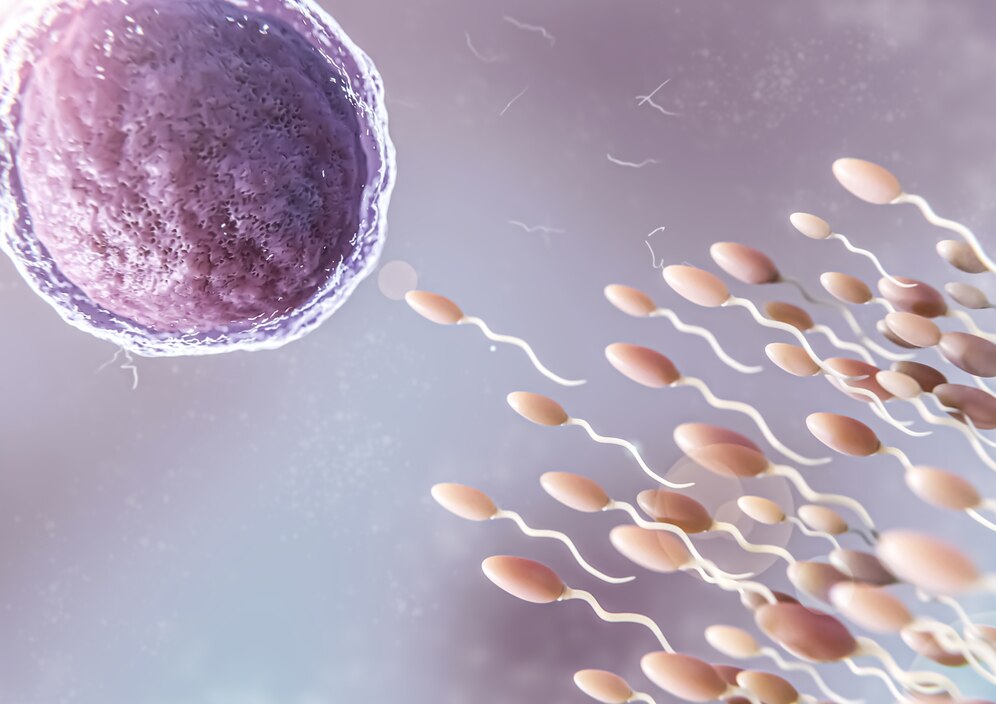

- Çocuk sahibi olma hayali kuran çiftler için tüp bebek tedavisi (IVF), modern tıbbın sunduğu en etkili yöntemlerden biridir...

Çocuk sahibi olma hayali kuran çiftler için tüp bebek tedavisi (IVF), modern tıbbın sunduğu en etkili yöntemlerden biridir. Van tüp bebek doktoru olarak hizmet veren Op. Dr. Muhammed Ferhat Kesmez, kadın hastalıkları, doğum ve infertilite (kısırlık) tedavilerinde uzmanlaşmış bir hekimdir. Kısırlık tedavisi, yumurta takibi, embriyo transferi ve tüp bebek uygulamaları konularında geniş deneyime sahip olan doktorumuz, en güncel ve bilimsel yöntemlerle çiftlerin ebeveyn olma hayallerini gerçeğe dönüştürmelerine yardımcı olmaktadır.

Tüp Bebek Tedavisi Nedir? Kimlere Uygulanır?

Tüp bebek tedavisi (IVF), doğal yollarla çocuk sahibi olamayan çiftler için geliştirilen yardımcı üreme tekniklerinden biridir. Kadın yumurtasının ve erkek sperminin laboratuvar ortamında döllenmesi ve ardından elde edilen sağlıklı embriyonun anne rahmine yerleştirilmesi esasına dayanır.DEVAMI